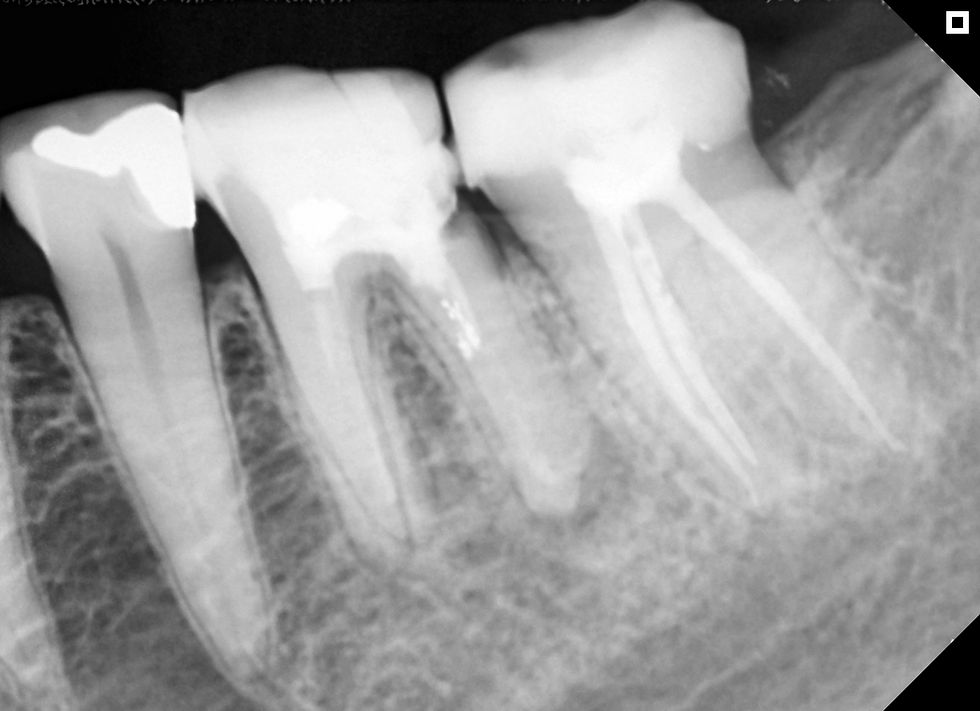

Dê uma olhada na radiografia pré-operatória, queixa principal do paciente perda de sensibilidade no lábio inferior esquerdo

À primeira vista? Este dente parece bem reto para a frente.

Há resina na câmara pulpar, então o acesso deve ser bastante difícil e os canais parecem bem abertos, então o retratamento deve ser fácil.

Mas, se você olhar mais profundamente, verá que este caso precisa de nós, como dentistas, para nos adaptarmos ao dente e à sua situação clínica. Mas o CBCT contou uma história diferente.

Veja como ficou esse canal radicular.